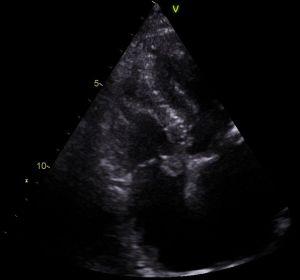

An echocardiogram is often requested for patients experiencing chest pain, and this imaging modality lends itself perfectly for the detection of myxomas.

Above: a rare finding of a myxoma on the right side of the heart in a patient referred for a suspected myocardial infarction. In this instance, the myxoma moves with opening of the tricuspid valve into the right ventricle during diastole, and returns to the right atrium during (ventricular) systole. This can be appreciated from the images below, where the image on the left is taken in diastole, and the image on the right during systole: